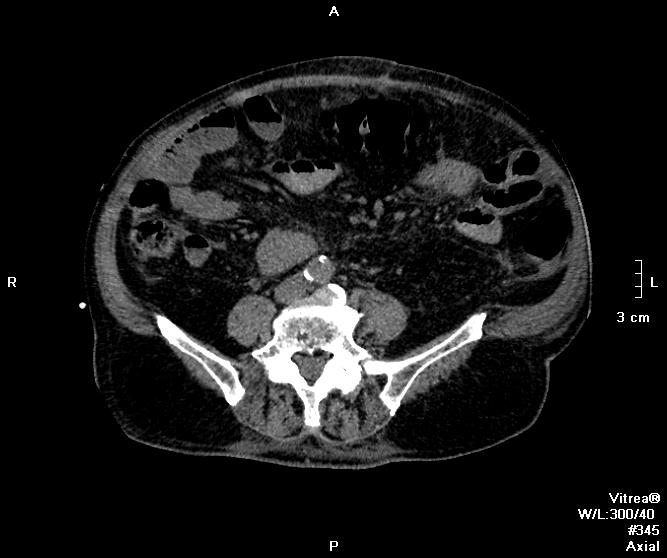

Пациент поступил ко мне через 6 дней после ушивания перфоративной язвы ДПК. УЗИ-сты увидели инфильтративно-жидкостные изменения в зоне оперативного вмешательства, пузырьки газа. Но смутило найденное образование в пространстве между правой долей печени и паранефрием. цель исследования - дифференцировать найденное между инфильтрацией и жидкостным скоплением.

Пациента готовили в течение 2 часов, перорально разведенный урографинчик дробно, и пол станканчика перед исследованием (это важно). Болюс в артериальную и венозную фазы.

мы имеем - задренированное околопеченочное пространство, жидкость в подпеченочном, левом поддиафрагмальном пространстве и по контурам селезенки (серозная), к передне-наружному контуру левой доли печени прилежит ограниченное жидкостное скопление

-ничего криминального между висцеральной поверхностью печени и правой почкой (паранефрий как им угодно) не вижу

-!!! в нативе желудок и петли кишечника не контрастированы - следы контраста в отдельных петлях тонкого к-ка (перед исследованиям он пил, по зонду ничего никуда - ни ни!!!), петли толстого и тонкого кишечника содержат умеренно повышенное количество воздуха и жидкого содержимого, с горизонтальными уровнями

- просвет верхне-горизонтальной ветви дпк в области оперативного вмешательства и зоны сегментарной пластики убудительно не прослеживаеся, представлен зоной инфильтрации, утолщенными стенками кишки, по наружному контуру воспаленных тканей лентовидно расположенные пузырьки воздуха - более вероятно воздух на фоне складок; затеков КВ нет

- воспалительные изменения в проекции лапаротомного доступа, в пжк передней брюшной стенки, в абдоминальной жировой клетчатке и межпетельно

- диверткулище мочевого пузыря

- инфильтрат в левой седалищно-прямокишечной ямке

- меня смущает не типичный вид артериальной фазы, и уж тем более венозной

Усиление коркового вещества слабое, задержка начала нефрографической фазы. диаметр почечным артерий около 5 мм, почечных вен -- 10мм. на 60 секунде отсутствует должное конрастирование вен, без признаков патологического сброса

и куда контраст делся из кишечника? (предположим - не развели в кувшинчике, но выпить-то перед исследованием мы ему дали)

ну не глюк ведь??? ни одна вена не усиливается! почему так???